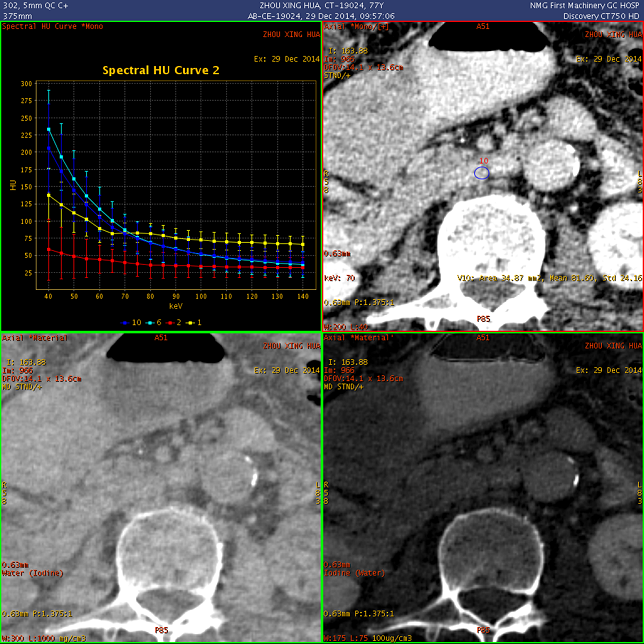

扫描参数 模式:GSI 550mA@0.8sec/rot@DC40mm@SFOV Body Large 螺距:1.375:1 造影剂注射方案 350mgI/100ml@70ml@3.5ml/sec Smartprep/TH120/AutoVoice Off 静脉期设置35s延迟;延迟期设置120s

观察不同期相显示:胃窦部及十二指肠区团块,碘基图呈高密度证明有强化(白箭); 胃及十二指肠壁呈明显增厚,范围较广,胃及肠腔明显狭窄(碘基图尤为明显); 肝左叶受压明显

病灶内部密度不均,最大径线:7 × 11cm; GSI曲线分析:增厚的胃壁与外凸的部分能谱曲线一致,证明巨大病灶起源于胃; 延迟期观察,对比剂通过未受明显影响,胃壁无明显僵硬

实质期能谱曲线分析,显示病灶与腹腔内正常淋巴结曲线已有区别